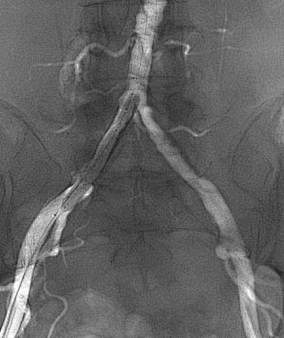

★ 造影评估

右侧股动脉翻山入路,经鞘管造影显示下肢动脉多发硬化改变。

左侧股浅动脉中下段局部重度钙化狭窄闭塞,左股浅动脉下段,腘动脉局部中度钙化狭窄。

★ 管腔准备

导管配合V-18 control wire通过病变段到达远端胫前动脉,交换V-14 control wire,引入Shockwave IVL M5(5.0×60mm)。冲击波球囊低压慢扩左侧腘动脉、股浅动脉下段钙化病变段(将球囊充盈至4atm后,激发震波,在完成一组脉冲后,将球囊缓慢充盈至6atm并持续60秒)

★ 术后造影

病变解除,管腔及血流恢复通畅,未见夹层及造影剂外渗